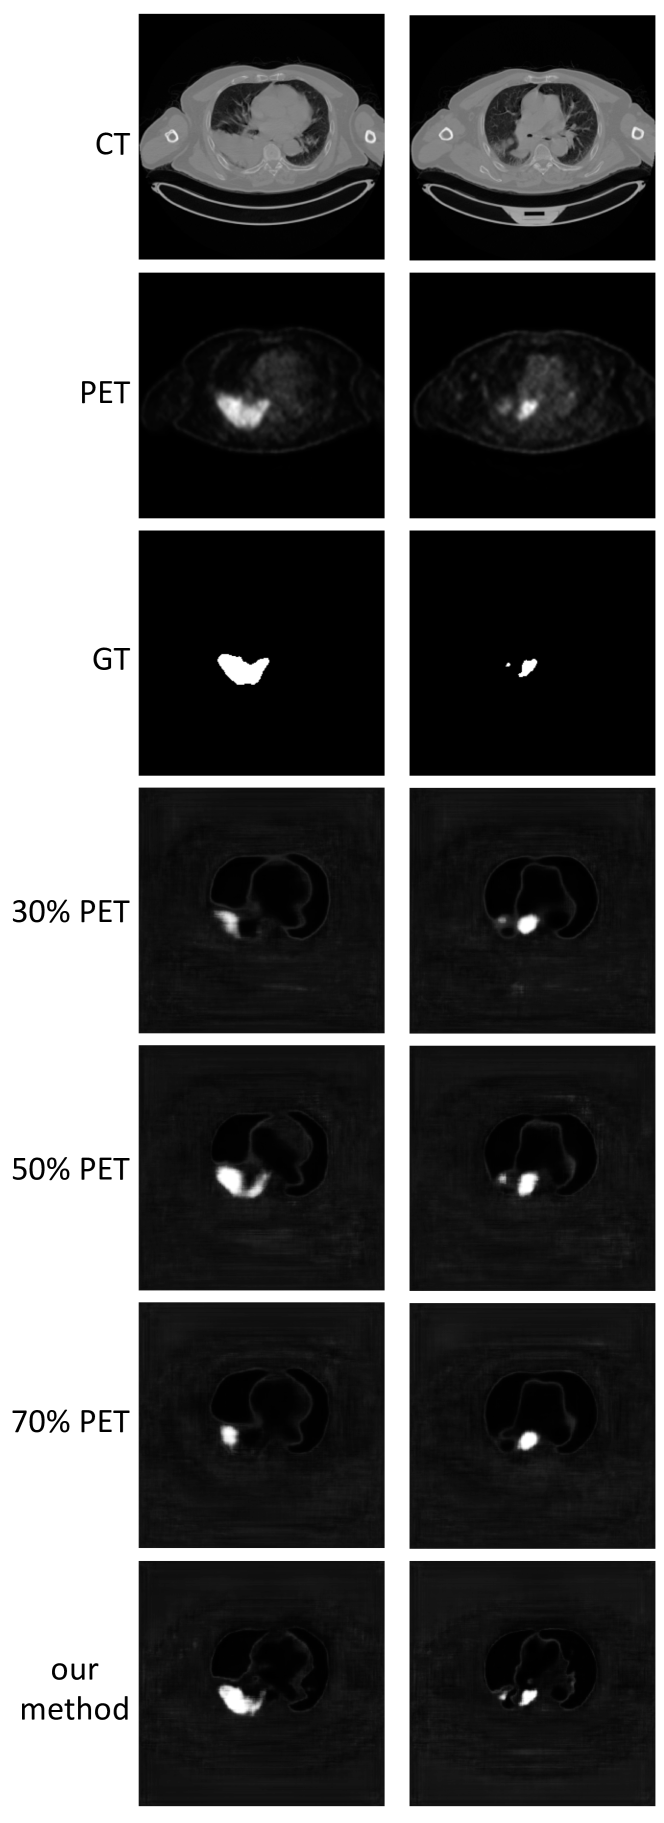

We extracted the feature fusion maps produced by the co-learning unit (see Section II-D) to examine the fusion ratios that were produced for an image with a tumor inside the lung field. This experiment was undertaken to confirm whether the fusion ratios that were automatically derived matched the well-established expectations. Further analysis on a heterogeneous tumor was performed for the Supplementary Materials (see Section S3). We also visually compared the results derived using our co-learning CNN’s spatially varying fusion to the results derived from using different uniform fusion ratios with the FS architecture. We used uniform fusion ratios that included mainly anatomical information (30% PET with 70% CT), equal information (50% PET and CT), and mainly functional information (70% PET with 30% CT).

Fig. 8 is a visual comparison of the results obtained by our co-learning CNN to the results obtained with uniform fusion; a larger version is included as Fig. S6 in the Supplementary Materials. The figure shows that our CNN has visually consistent tumor detection across both studies. In contrast, the figure visually shows that a uniform fusion ratio may not be optimal for different studies; equal (50%) PET and CT is the better ratio for detecting the tumor in the study in the left column, while reduced (30%) PET is the better ratio for the detecting the tumors in study in the right column. The uniform fusion results were sensitive to the fusion ratio and the specific PET-CT images being processed, and across different studies produced probability maps that either missed tumors or overestimated the tumor area.